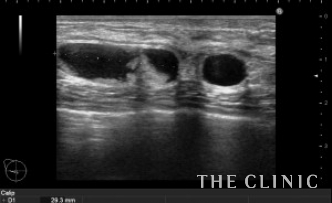

本日も他院の豊胸後のしこりです。

最大3㎝の充実性のしこりとオイルシストが混在していました。

左が充実性のしこりです。右がオイルシストです。